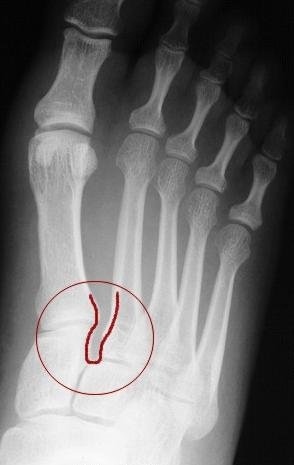

Figure 3: Abnormal AP xray of right foot. The red circle represents the Lisfranc joint between the 1st and 2nd metatarsals and the medial cuneiform bone. Notice the abnormally large space (outlined by red line) between the two metatarsal bones (compare to Figures 1 & 2) which indicates that the ligament complex has been torn allowing for the bones of the Lisfranc joint to begin to dislocate (sublux).

The most common injury to the Lisfranc joint occurs at the joint involving the 1st and 2nd metatarsals and the medial cuneiform. If the ligaments between the medial and mid cuneiforms are disrupted, or between the 1st, 2nd mt and the medial cuneiform, then the bones separate and the normal alignment of the joints is lost.